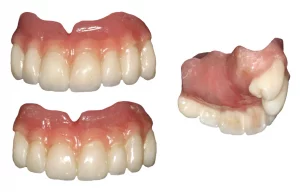

Below left, you can see the inside of his denture with the metal sleeve that fits onto the bar. The custom-made bar is pictured on the right. Although the bars look different initially, patients love the bar’s stability for their dentures. The dentures are simple to remove and place. There’s no movement on eating, and cleaning and maintaining the implants long-term is easier.